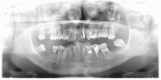

Myositis ossificans is a disease that is characterized by nonneoplastic, heterotopic bone formation within a muscle. Myositis ossificans traumatica, also called myositis ossificans circumscripta, is a disease in which muscles are ossified presumably following acute trauma, burns, surgical manipulation, or repeated injury. It is often remitted after surgical excision though some patients have repeated recurrences. Myositis ossificans traumatica of masticatory muscles is not frequently reported in the literature, with the most common clinical finding being a progressive limitation of motion in the mandible. The aim of this article is to present and discuss a case of myositis ossificans traumatica of the left medial pterygoid muscle and to review the literature of myositis ossificans of the masticatory muscles.